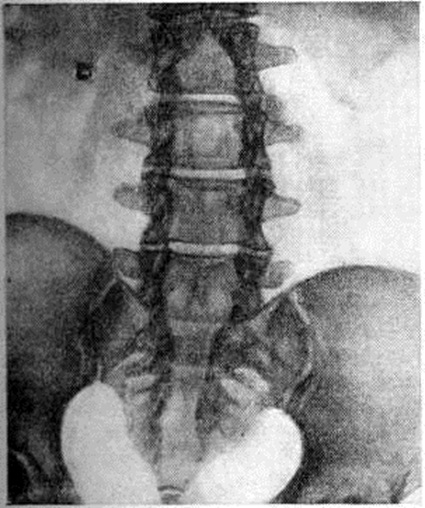

Локализация расщелины в теле или дуге позвонка может быть самой различной (рисунок 2). Рентгенологически легче распознаются расщелины, ориентированные в сагиттальной плоскости, которые лучше видны на рентгенограмме в прямой проекции. Расщелины в боковых отделах дуг и тел видны на рентгенограммах в боковой проекции, а иногда только на томограммах. При локализации в телах позвонков (spina bifida anterior) щель делит тело позвонка на две части, каждая из которых имеет на рентгенограмме в прямой проекции клиновидную форму. Чаще обе части тела позвонка расположены симметрично, напоминают по виду крылья бабочки — так называемый бабочковидный позвонок. Однако клиновидные части тела позвонка могут быть и асимметричными (рисунок 3). В процессе роста тела соседних позвонков приспосабливаются к форме аномальных позвонков.

При выраженных нарушениях развития дуг позвонков на рентгенограммах обнаруживают их обширные дефекты с отсутствием изображения остистых отростков, задних отделов, а иногда и суставных отростков и даже ножек дуг (рисунок 6). Обнаружение Спина бифида должно побудить к поиску других проявлений спондилодисплазии (локальных сужений позвоночного канала, межпозвоночных отверстий, вариантов расположения суставных отростков, деформации тел позвонков, чаще клиновидной, и другие).